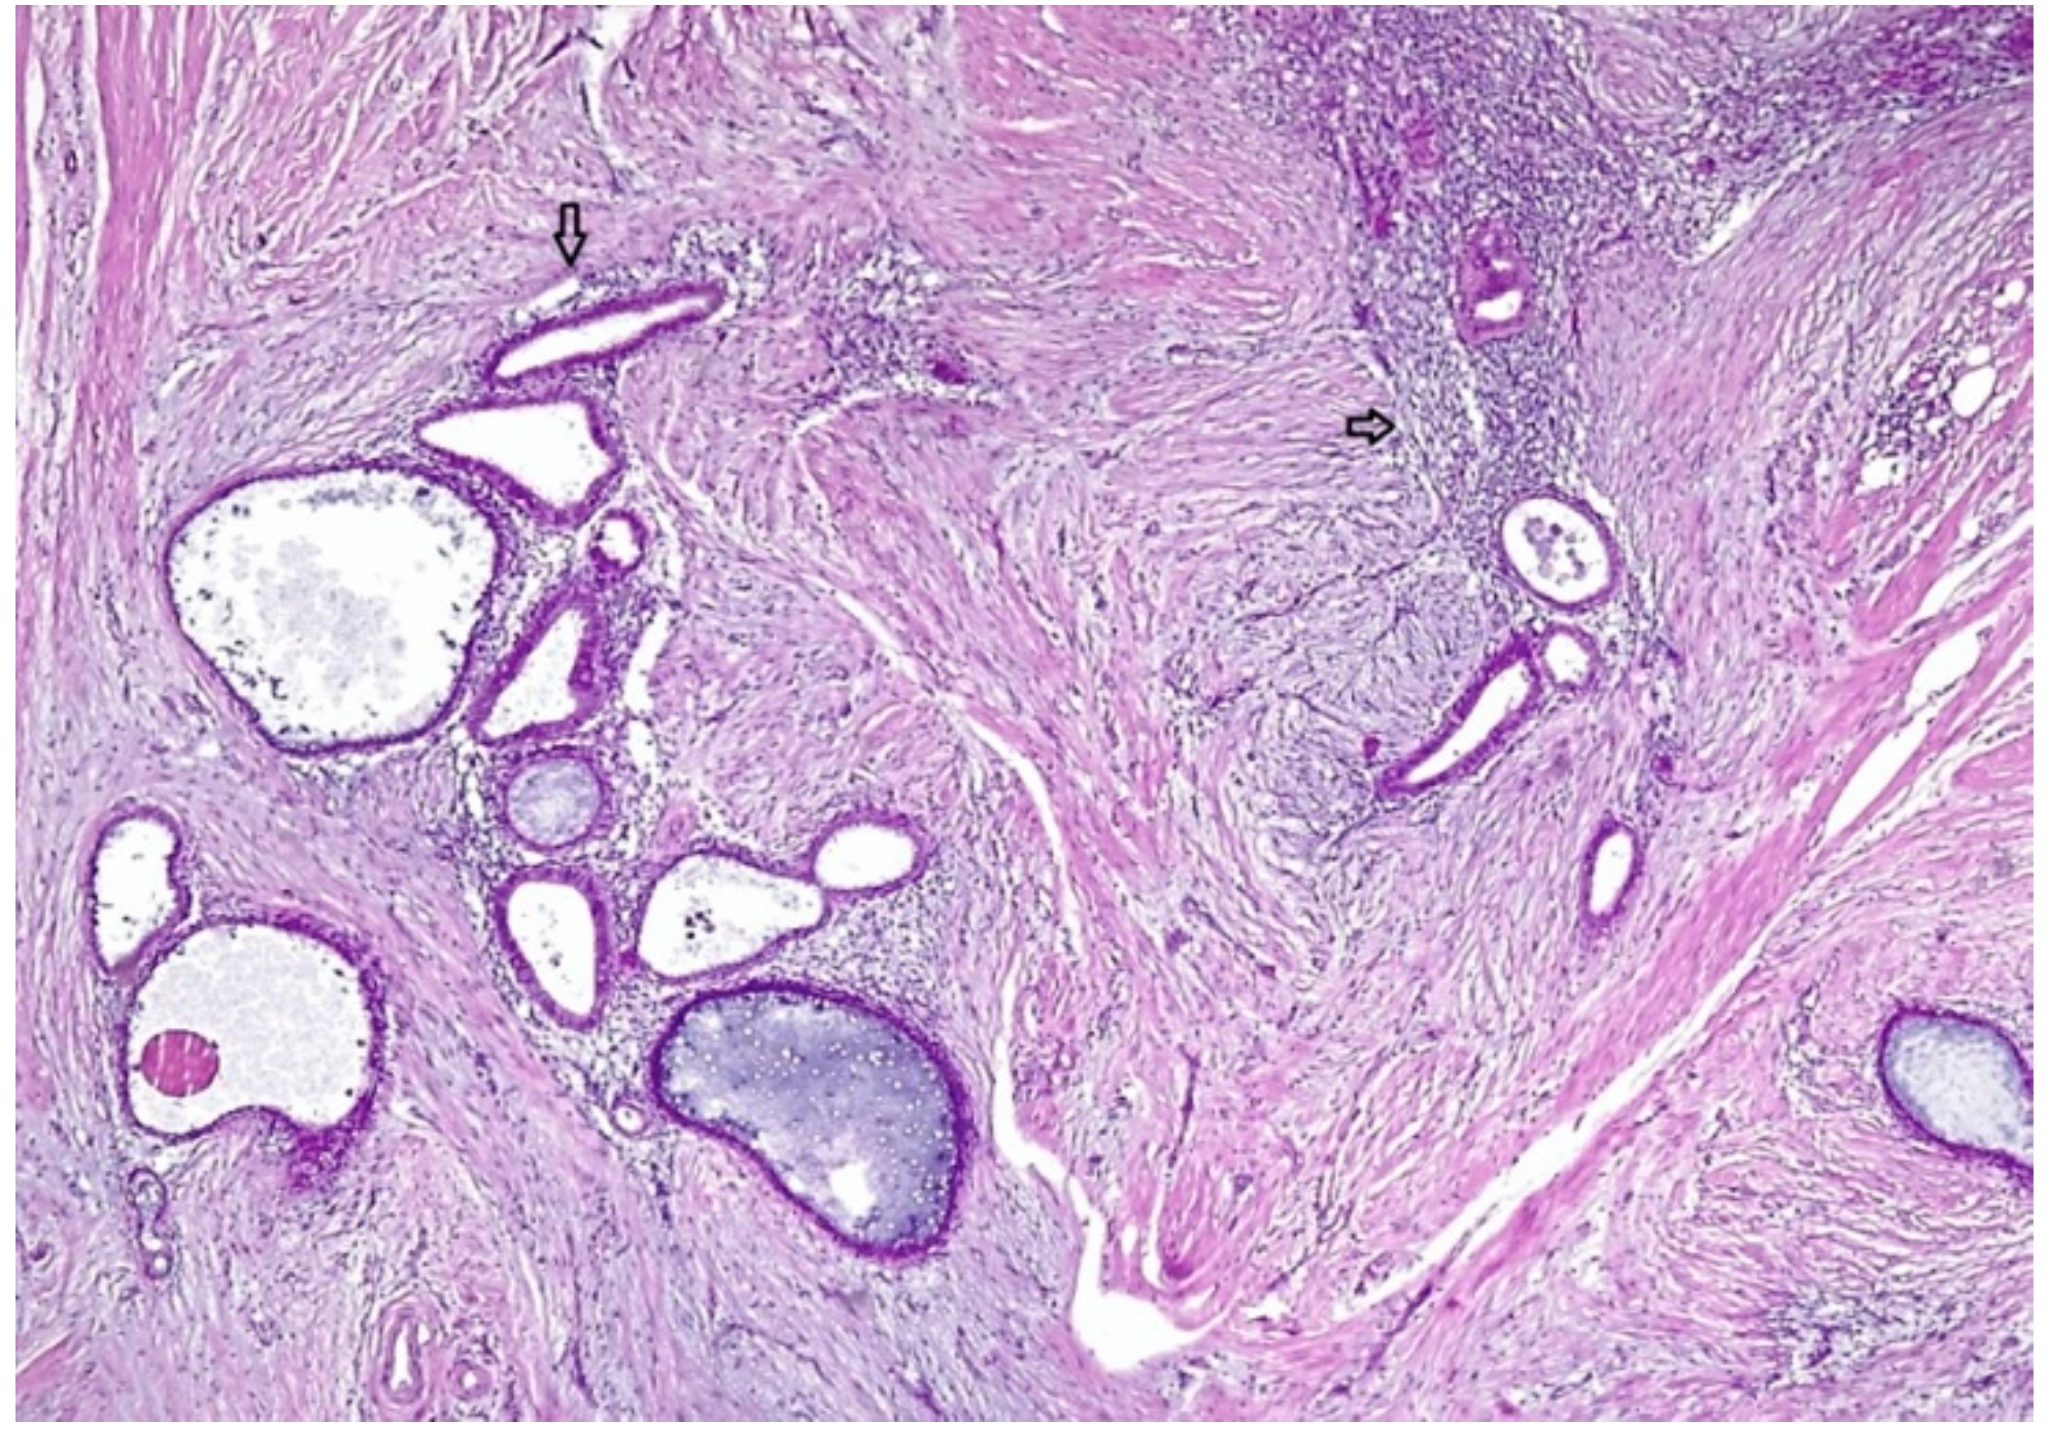

2.1. Case 1